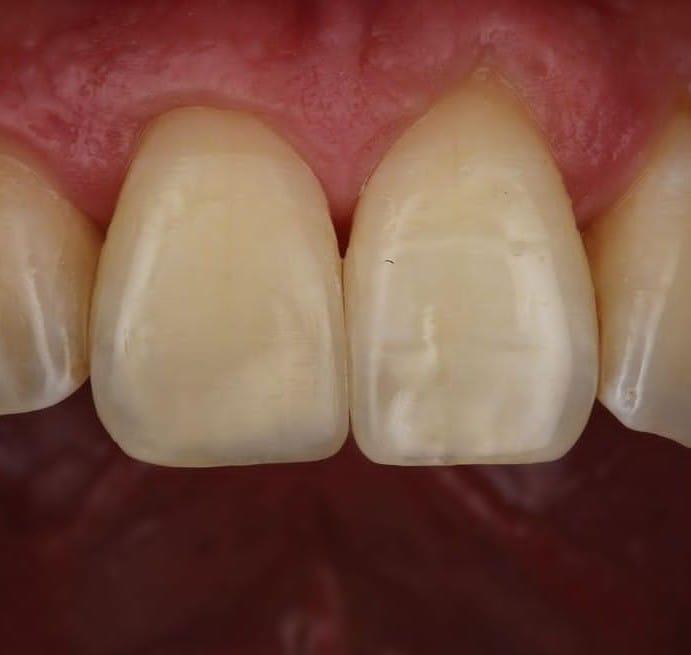

Es un procedimiento quirúrgico dental que consiste en la remoción de una parte del tejido gingival (encía). Se realiza principalmente por dos razones:

1. Estética: Para mejorar la apariencia de la sonrisa, por ejemplo, en casos de “sonrisa gingival” donde se muestra mucha encía al sonreír.

2. Terapéutica: Para tratar enfermedades periodontales, eliminando tejido afectado por inflamación crónica, permitiendo una mejor limpieza de las bolsas periodontales.